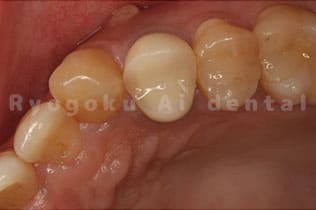

Case10

-

術前

術後

- 原因

- 左下6番欠損

- 治療内容

- インプラント治療

- 治療費用

- 約600,000円

左下の奥歯に歯を入れて欲しいとのことでご来院された患者様です。インプラント治療が最適とご提案させて頂き、治療を行いました。経過も良好で、大変満足して頂けました。

<リスク・副作用>

治療後、痛みや違和感、出血、腫れなどが出る事があります。喫煙者、糖尿病などの方の場合、歯が生着しない場合があります。